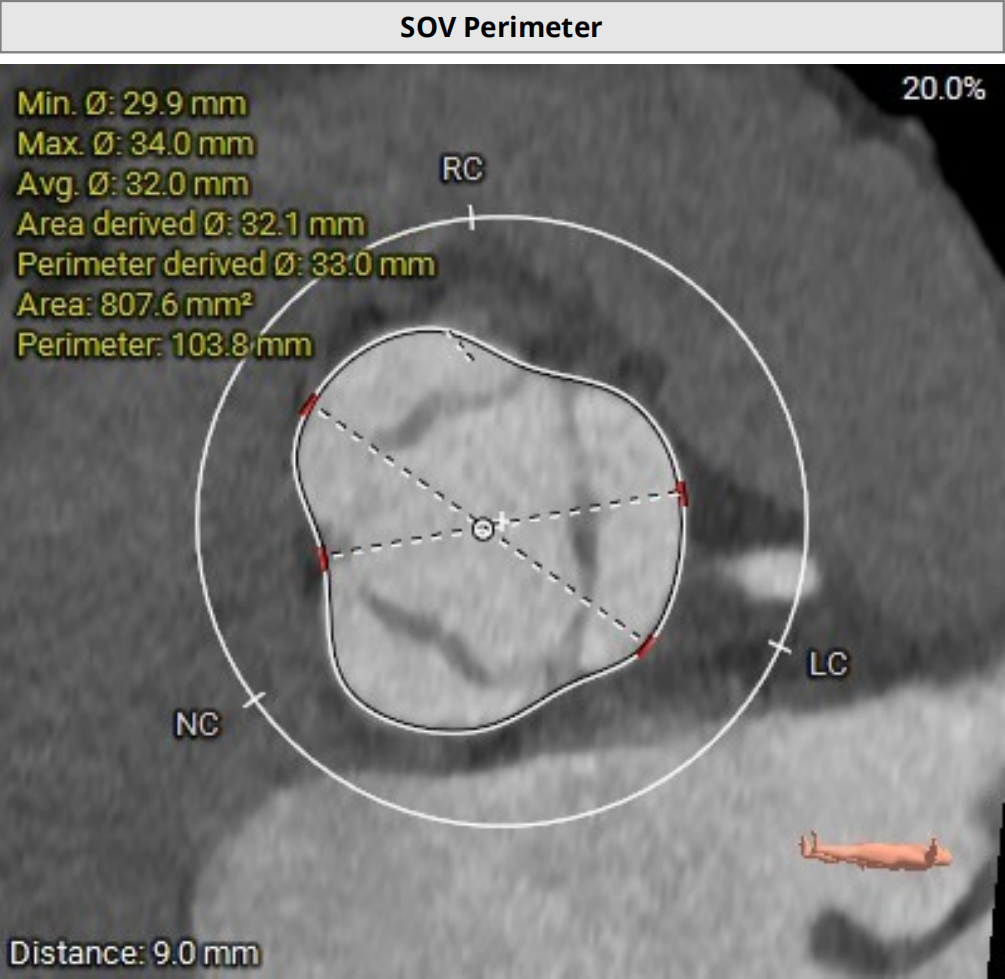

2026年伊始,TaurusTrio经导管主动脉瓣系统在复旦大学附属中山医院,浙江大学医学院附属第二医院,中国医学科学院阜外医院,首都医科大学附属北京安贞医院,四川大学华西医院等多家临床中心成功开展上市后全国首批植入。这不仅是TaurusTrio正式走向广泛临床应用的重要里程碑,更标志着中国单纯主动脉瓣反流介入治疗正式迈入了“心键合璧”的全新纪元。